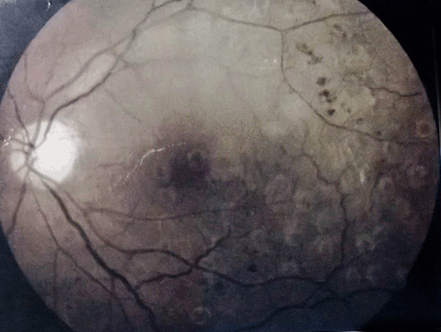

At sixth month funduscopic examination along with an OCT revealed presence of epiretinal membrane and a prominent foveal scar (Figure 2) and visual acuity improved to 20/100.

Figure 2: Six months later, an optical coherence tomography revealed persistence of the epiretinal membrane and a prominent foveal scar.